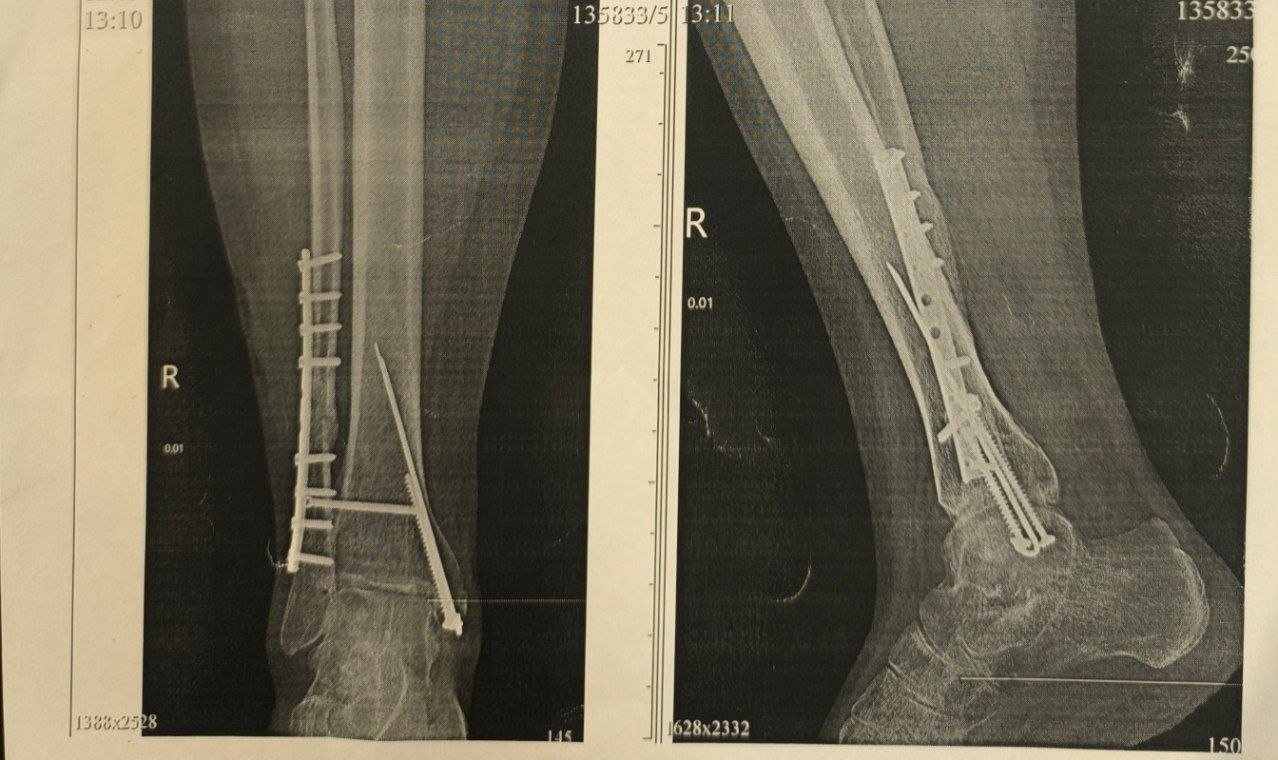

Медицинские документы фиксируют вред здоровью, который получил мальчик: «полный поперечный перелом нижней трети диафиза малоберцовой кости со смещением, полный оскольчатый внутрисуставной перелом внутренней лодыжки большеберцовой кости, разрыв дистального межберцового синдесмоза, подвывих стопы» — простыми словами: нога подростка была раздроблена, кости сместились, связки порваны, сустав вывихнут.

В день травмы мальчику сделали закрытую репозицию — кости вправили без разреза. Через три дня ногу разрезали, поставили пластину и винты. Спустя несколько месяцев металлоконструкцию удалили, но сустав за это время разрушился. Поэтому Кириллу потребовалась ещё одна операция. Семья поехала в федеральный центр детской травматологии и ортопедии в Санкт-Петербург, там кость пришлось ломать и сращивать заново.

Кириллу пришлось сломать уже сросшуюся кость, чтобы срастить её заново

Снимок ноги Кирилла, где видно какая кость сломана